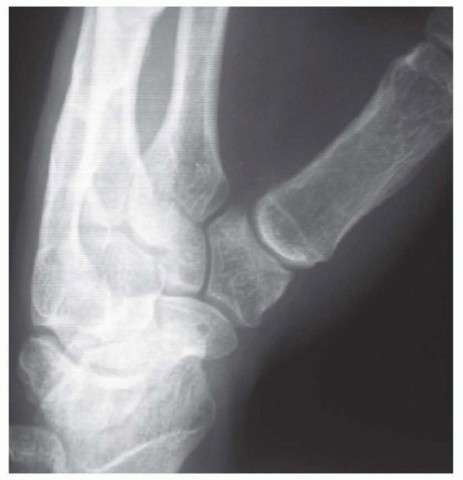

Our imaging protocol must be exhaustive to provide a three-dimensional understanding of the fracture morphology. Standard hand radiographs are insufficient due to the unique 30-degree pronated position of the thumb relative to the rest of the carpus. A True AP View of the Thumb CMC Joint (Robert's view) is obtained with maximal forearm pronation, placing the dorsum of the thumb flat on the cassette. This optimizes visualization of the joint space and the critical ulnar fragment. The True Lateral View (Billing and Gedda) is achieved with the hand pronated 20 degrees and the thumb flat on the cassette, with the X-ray beam tilted 10 degrees from vertical in a distal-to-proximal direction.

Image